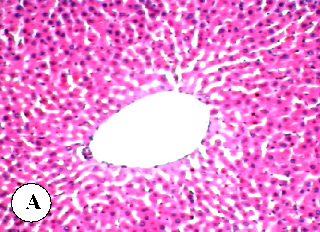

Figure 7

Figure 7 Micrograph

Additional liver histopathology from a different plant oil treatment group, demonstrating the comparative hepatoprotective effects of various plant oils against diazinon toxicity.

Protective effect of some plant oils on diazinon induced hepatorenal toxicity in …